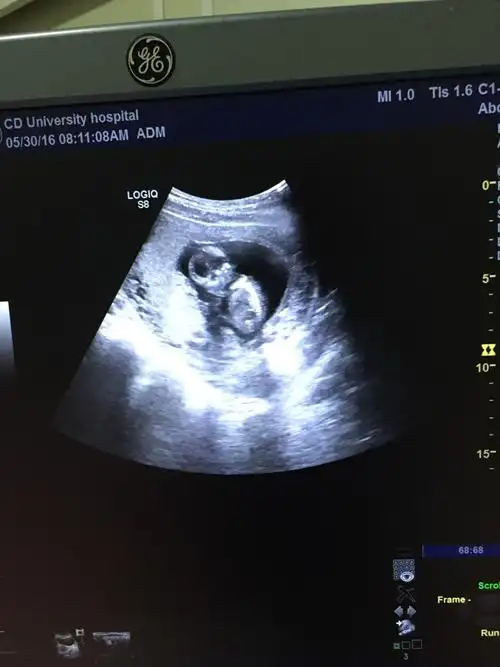

热 12周-14周b超图像可分辨男女

孕期14周,胎儿b超图片,麻烦帮忙看一下是否正常

怀孕14周b超看男女准确吗?

14周照的超音波看起来是男宝吗